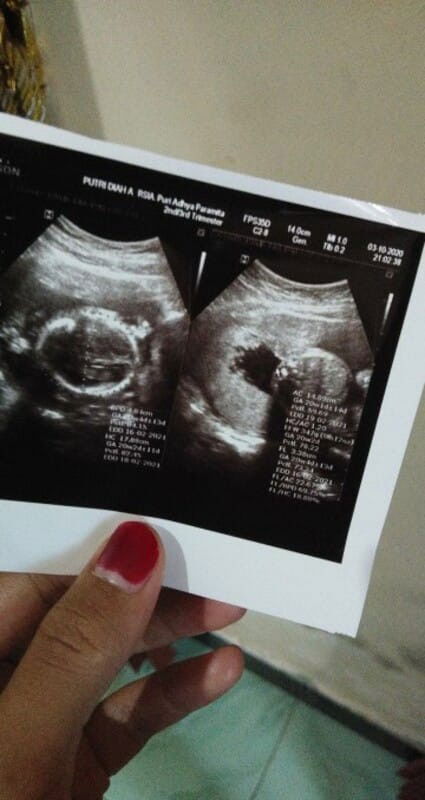

Assalamualaikum, disini aku mau cerita tentang kehamilanku, # Aku awal ngeflek (berupa lendir keputihan berwarna coklat dan hanya segaris)UK 5mg selama 2 hari (tdk mules,tdk kram, tdk sakit pinggang), darisitu langsung usg masih berupa kantong dan dikasih penguat kandungan Utrogeston dosis 200ml sebanyak 20 tablet. # Selang 1 minggu aku flek lg (masih dalam bentuk yg sama,yaitu lendir seperti keputihan berwarna coklat) selama 3 hari (tanpa kram,mules dan sakit pinggang), tepat diusia kehamilan 6w2d, terakhir flek tgl 2 juli 2020,alhamdulillah sampai sekarang udh ga ngeflek lagi #Di tgl 16 juli 2020 (8w2d)aku USG pake 2 dimensi Hasil USG usia kandungan ku 9w2d(masih berupa kantong😥),padahal sesuai HPHT usia kandunganku baru menginjak 8mg, #aku ngerasa diusia kandunganku 7 mg tanda2 kehamilanku mulai berkurang😥,seperti mual muntah yg gak sperti biasanya, dan payudara terasa kenyal (gak sakit,gak nyeri, gak kenceng)😥😥 #setiap hari aku pptest, hasil pptest bangun tidur garis 2 merah terang, tp nanti klo udh siang/sore, pptest hasil garis 2 samar😥😥 APAKAH ADA YANG SAMA PENGALAMAN NYA SEPERTI AKU??? BISA SHARING DIKOMENTAR YA BUN... Besok malem baru mau usg, Doain ya bunda2 yg ada di Apk TAP,semoga kantong kehamilan ku sudah ada janin dan detak jantungnya, Aamiin Yarobbal'alamin😇🙏🙏 Gambar 1 pptest siang Gambar 2 pptest bangun tidur